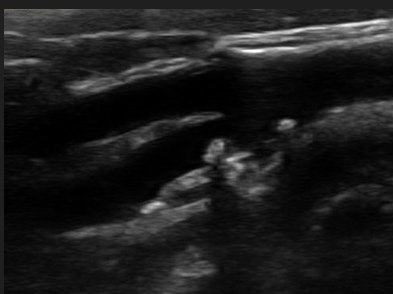

Patient is 38 y/o female with stroke like symptoms. No risk factors or medical history. You take this image of distal ICA.

1. What is the sonographic description of distal ICA?

2. What does this indicate or what is possible diagnosis?

3. Is this related to atherosclerosis?

4. What is important in patient clinical presentation for possible diagnosis?

5. Which other vessels most likely impacted by this?

string of pearls

FMD

No (congenital abnormality)

young female

Renal artery’s